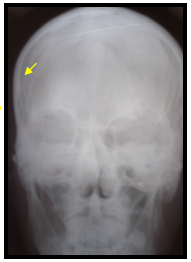

Закрытый перелом головы